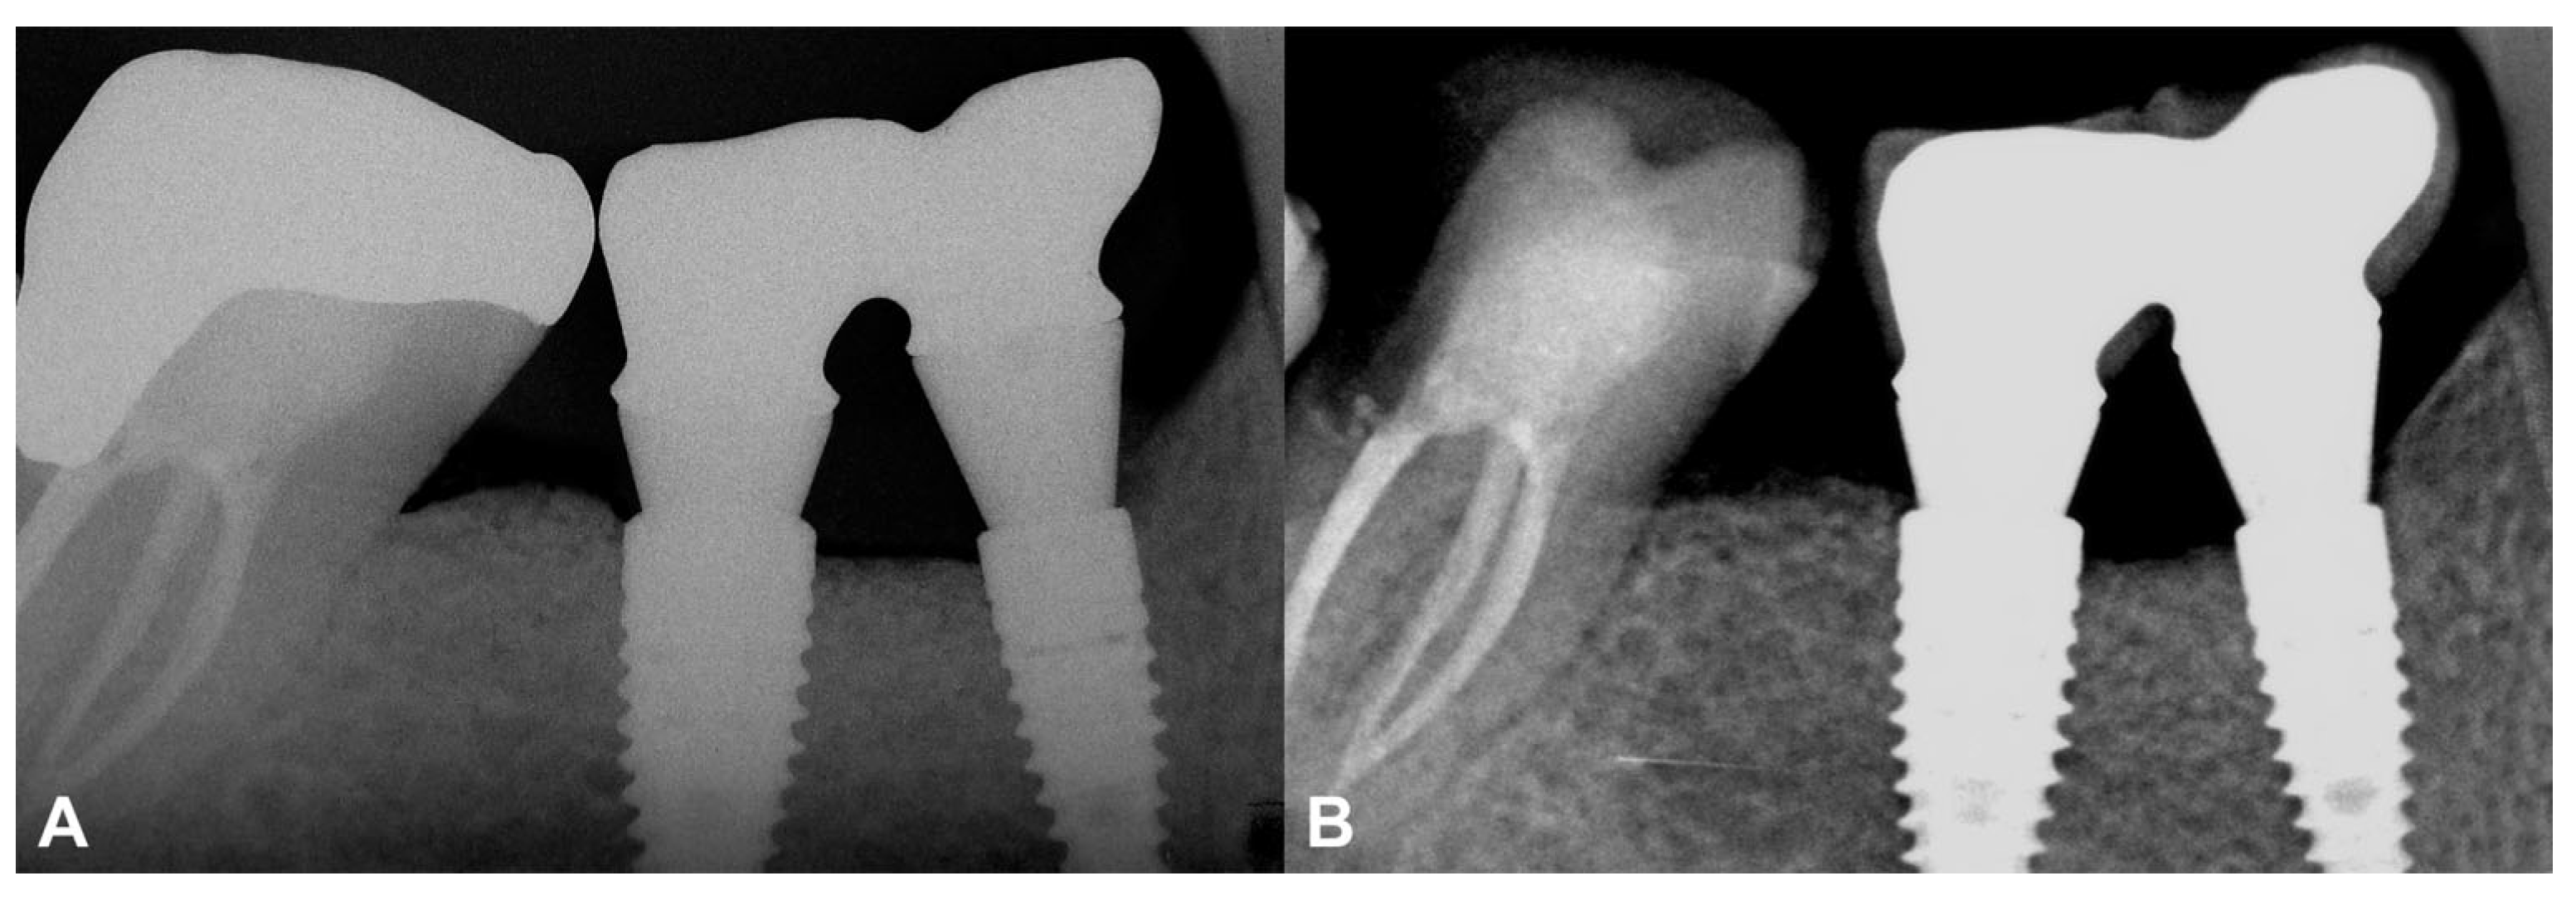

3.2.2. Short-Term Volumetric Hard Tissue Gain and Long-Term Follow-Up

Compared to the baseline CBCT scan, a 0.36 cm3 hard tissue gain could be detected after the six-month healing period (Figure 6A,B). A 2.77 mm vertical hard tissue gain was detected at the deepest point of the defect, while horizontal hard tissue gains were 4.37 mm, 4.33 mm, and 3.37 mm at 1, 2, and 3 mm apical to the top of the alveolar crest, respectively (Figure 6C,D).

At the two-year follow-up, the marginal bone was stable, and no resorption was visible (Figure 7). The data are summarized in Table S2.

The second presented case used the magnesium membrane with a more conventional approach. By elevating a split-thickness flap on the buccal aspect, horizonto-vertical hard tissue augmentation occurred. In addition, due to the rigidness of the membrane, no tenting screws were necessary to support the barrier from below [7]. Volumetric hard tissue gain was found to be similar to results acquired with PTFE membranes [7,23] or titanium meshes [6].

The current study has reported two-year follow-ups using the resorbable magnesium barrier membrane. The IRs acquired after the delivery of the final prosthetic restoration were compared to those at the two-year follow-up and stable marginal bone contours were observed. In both cases, a stable peri-implant hard and soft tissue environment was established, and neither of the inserted implants showed marginal bone resorption or peri-implant inflammatory processes.